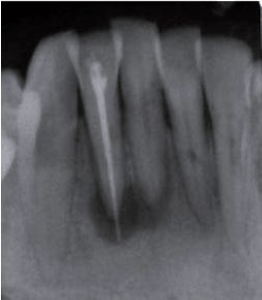

Paciente do gênero feminino, 33 anos, procurou atendimento odontológico queixando-se de dor há algum tempo no dente 42 durante a mastigação. Relatou que tinha feito endodontia no dente em questão havia alguns meses. Ao exame radiográfico, verificou-se presença de área radiolúcida no terço apical dos dentes 41 e 42 e sobreobturação no 42. O dente 41 respondeu negativamente ao teste de vitalidade.

Qual o tratamento mais indicado?